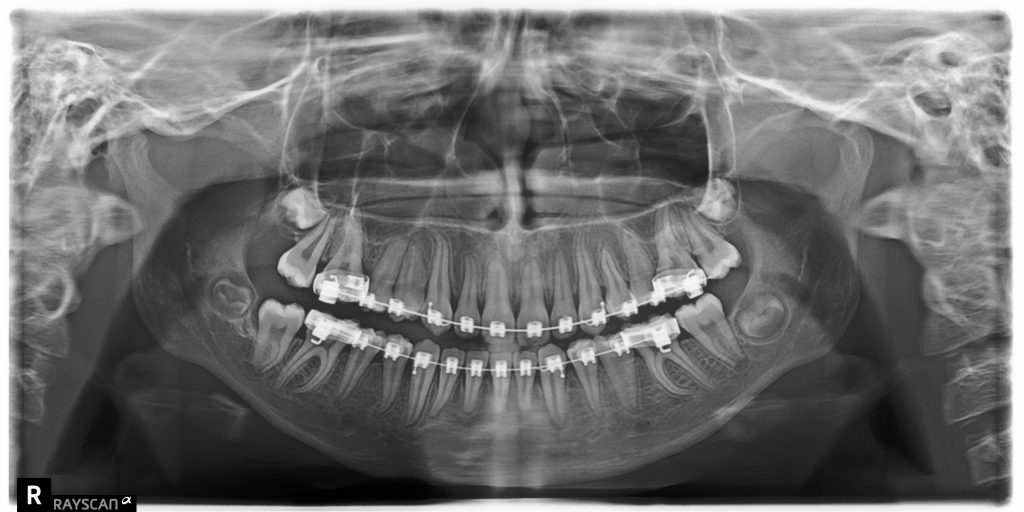

Streszczenie: Tomografia stożkowa jest nowym narzędziem diagnostycznym w stomatologii, którego możliwości stale wzrastają. Istnieje wiele nazw tej techniki, a stosowany powszechnie skrót pochodzi od anglojęzycznej nazwy cone beam computed tomography, czyli tomografia komputerowa z wiązką promieniowania w kształcie stożka. Druga z często używanych nazw to stomatologiczna tomografia wolumetryczna (digital volumetric tomography – DVT) (1). W artykule przedstawiono przykłady przypadków klinicznych napotkanych w codziennej praktyce ortodontycznej, w których autorzy zdecydowali się na poszerzenie diagnostyki o CBCT.

Summary: Cone beam computed tomography is a new diagnostic tool in dentistry, with ever rising possibilities. The technique is known under many names, but the popular abbreviation comes from the English term ‘cone beam computed tomography’, which denotes computer tomography where the X-rays form a cone. The other common name is digital volumetric tomography – DVT (1). The article presents the [...]